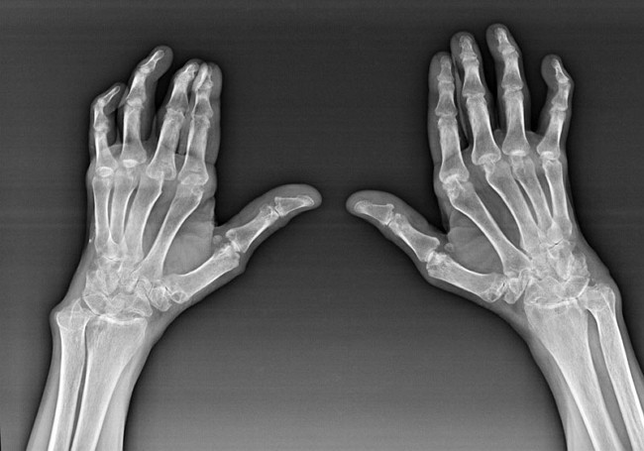

Reumatoïde artritis

Reumatoïde artritis is een ziekte waarbij het menselijke immuunsysteem de eigen weefsels van het lichaam beschadigt. Met andere woorden, reumatoïde artritis is een auto -immuun pathologie. Deze ziekte is ook systemisch, omdat veel weefsels ermee worden beïnvloed (spieren, gewrichten, schepen, etc.) en organen (Hart, nieren, longen, enz.) in het lichaam.

Ondanks het feit dat reumatoïde artritis een systemische ziekte onder IT is, lijden de gewrichten in grotere mate, terwijl de laesie van andere weefsels en organen op de achtergrond is. Met deze ziekte kunnen bijna alle soorten borstelgewrichten worden beïnvloed (polshorloges, carpaalpaden, metacarpal-phalanx, interphalanx-gewrichten). De laesie is meestal symmetrisch (die. Dezelfde gewrichten worden beïnvloed) Op beide handen, vergezeld van zwelling, pijn in beschadigde gewrichten. 'S Ochtends, tijdens het heffen van bed, is er enige stijfheid in de aangetaste gewrichten, die ongeveer 1 uur kunnen duren en dan zonder sporen kunnen verdwijnen.

Heel vaak met reumatische artritis nabij de getroffen gewrichten van de borstel (vaker de piano-phalanx, interfalanx gewrichten) Reumatoïde knobbeltjes verschijnen. Ze zijn een afgeronde formatie die zich onder de huid bevindt. Op de borstel ontstaan deze formaties het meest op de achterkant. Op palpatie zijn ze dicht, inactief, pijnloos. Het aantal van hen kan variëren.